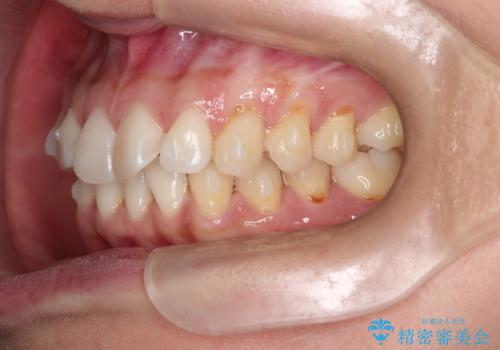

重度のガタガタのインビザラインによる非抜歯矯正

- 全体的なガタガタを気にされて来院されました。

抜歯矯正も考えられる状態でしたが、ご本人的になるべく歯を抜かない矯正を希望されました。

奥歯を後方に移動させるのと、歯と歯の間にわずかに隙間を作ることでスペースを確保して、抜歯をせず歯を並べる計画としました。

ガタガタの度合いが大きかったので少し時間がかかりましたが、非常に協力的な患者様でしたので、抜歯をせず計画通りに治療を終えることができました。